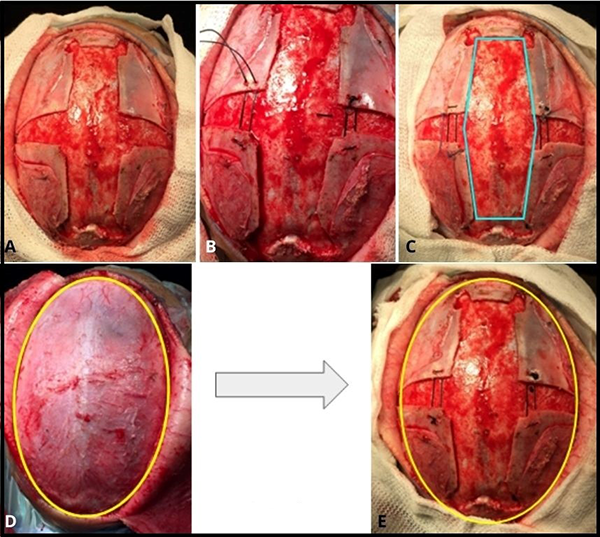

FIGURA 15: A- Sagitectomía y osteotomías en “V” bilaterales. B- Uno de los lados ya ha sido traccionado. C- Tracción en ambos lados. Nótese el cambio de conformación que toma la sagitectomía, ensanchándose en su punto medio. D y E - En amarillo se aprecia el cambio de conformación que adopta la calota.

FIGURA 16: Paciente operado a los 4 meses de edad. A- 2 meses después de la cirugía. B- 9 meses posterior a la cirugía. C y D- 2 años posterior a la cirugía.